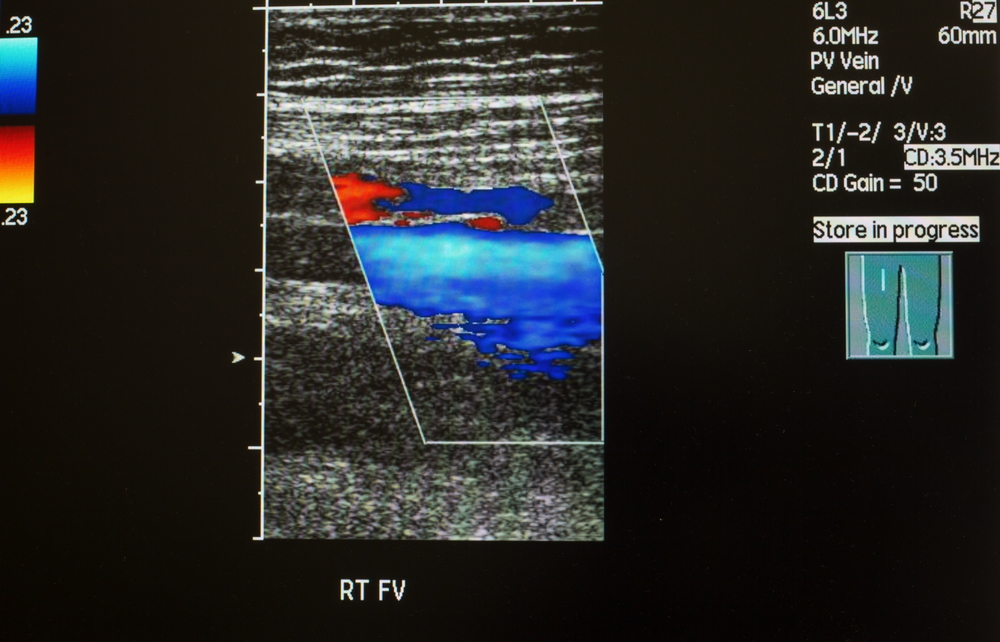

Принцип УЗДГ основан на использовании УЗ-аппарата с функцией допплерометрии, основанной на эффекте отражения Допплера. Испускаемый специальным датчиком сигнал проходит в ткани и отражается от клеточных элементов крови. Частота сигнала изменяется в зависимости от скорости кровотока, и эти колебания фиксируются программой, которая после обработки полученных данных составляет заключение о качестве кровообращения в исследуемых сосудах. Кроме этого, во время обследования изучается состояние стенок сосудов и клапанов вен. Получаемые результаты исследования позволяют специалисту не только ставить диагноз, но и оценивать степень тяжести заболевания.

Перед выполнением УЗДГ пациент оголяет конечности. Врач может попросить больного занять положение стоя или лежа. После этого он наносит гель на кожу и начинает перемещать по ней датчик. Благодаря сканированию изображение сосудов получается на экран монитора и обрабатывается компьютерной программой.

Что покажет ультразвуковая допплерография сосудов нижних конечностей

При выполнении УЗДГ могут получаться данные о следующих параметрах:

- диаметр, форма и место расположения вен и артерий;

- состояние стенок вен и артерий;

- скорость кровотока;

- работоспособность клапанов вен;

- присутствие тромбов, их структура, склонность к флотации, размер и плотность;

- наличие атеросклеротических изменений;

- присутствие рефлюкса (обратного заброса крови) при варикозной болезни;

- наличие артериовенозных мальформаций.